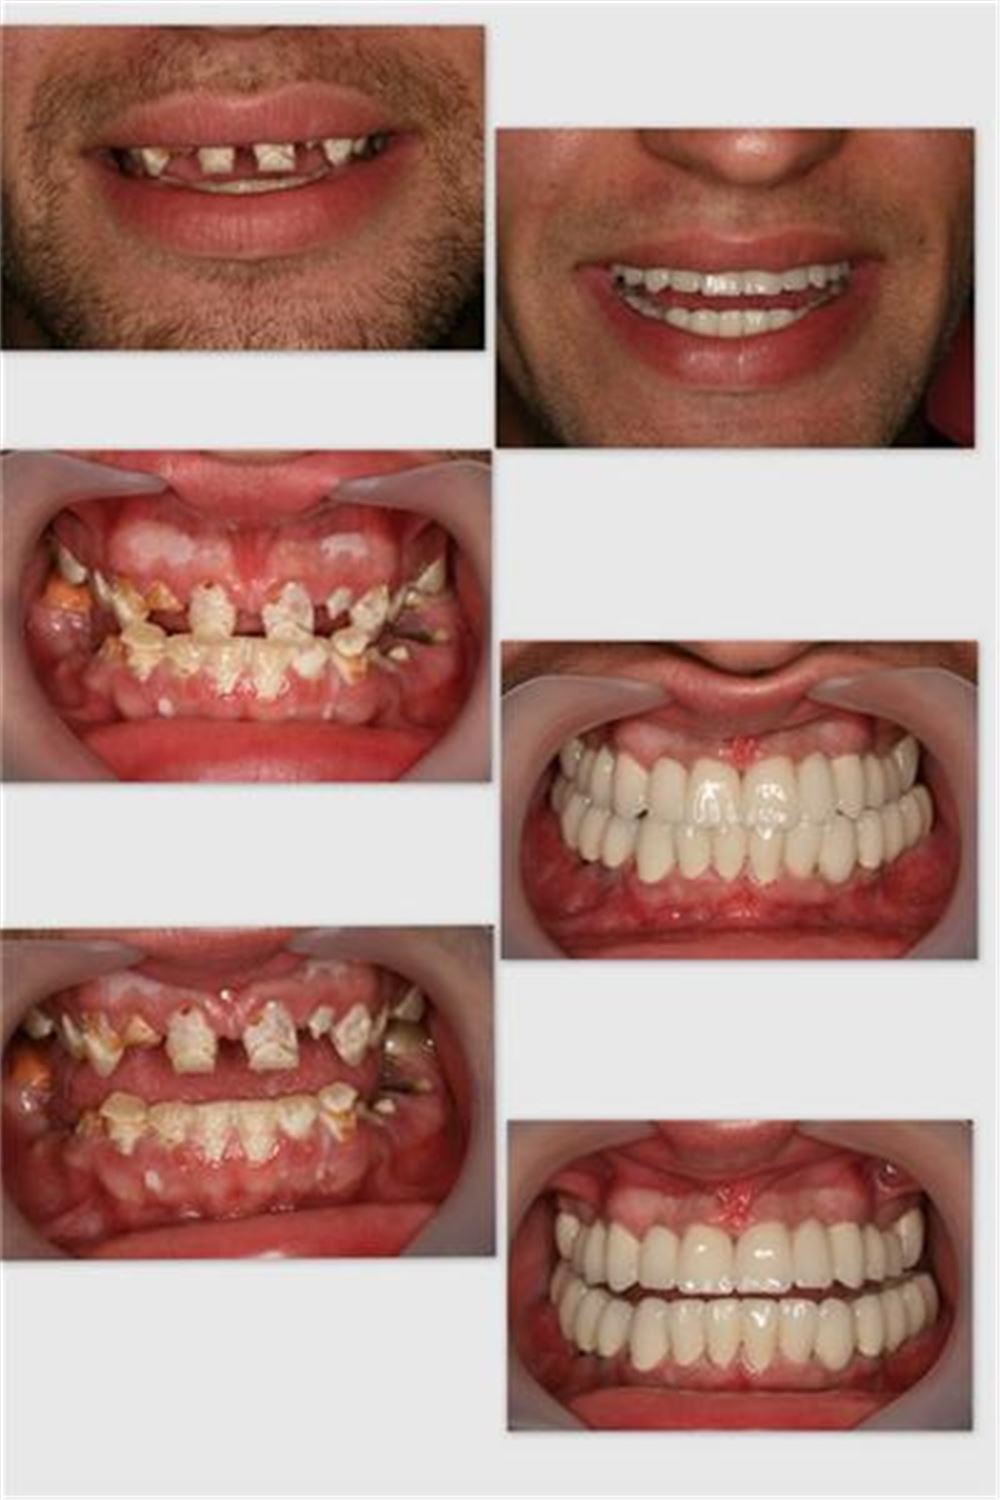

depigmentasyon+gingivektomi+implantx8+Implant supported porcelain fused to metal crown (28 units)

before&after